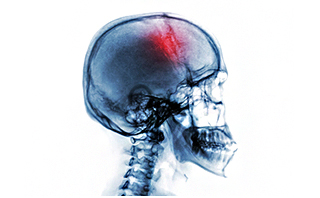

通常颅骨缺损小于3cm者多无症状,施行颞肌下减压术或枕下减压术后,有肥厚的肌肉及筋膜覆盖并在缺损区可以形成坚韧的纤维性愈合层,起到原有颅骨对脑的保护作用,在临床上亦无任何症状, 直径3cm以上的缺损,特别是位于额部有碍美观和安全的缺损,常有这样或那样的症状。

1、颅骨缺损处局部表现:局部有胀痛,缺损边缘疼痛,不能忍受的脑搏动,缺损部高位时头皮向颅内陷入;缺损部低位时,头皮甚至合并部分脑组织,脑室向外膨出。

2、颅骨缺损综合征:主要表现为头痛,头昏,患者对缺损区的搏动,膨隆,塌陷存恐惧心理,怕晒太阳,怕震动甚至怕吵闹声,往往有自制力差,注意力不易集中和记忆力下降;或有忧郁,疲倦,寡言及自卑。

3、长期颅骨缺损:有脑膨出或突出时,脑组织可萎缩及囊变,小儿颅骨缺损随脑组织发育而变大,影响正常脑发育而出现智力偏低;成年人可出现反应迟钝,记忆力下降甚至局灶性神经系统症状,体征,脑膜-脑瘢痕形成时可伴癫痫。

注意:颅骨缺损是颅脑损伤、颅骨骨瘤等开颅术后常见后遗症。当缺损范围直径超过3厘米时,不仅严重影响患者美观,而且会出现多种临床表现如头痛、头晕、情绪改变、缺损区搏动等,甚至可以可能诱发癫痫等严重的疾病,严重影响患者正常的工作和生活。